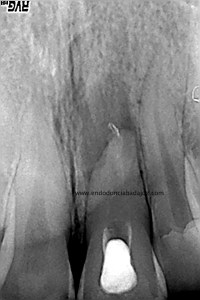

La paciente fue llamada a revisión al año:

Y más tarde, a los dos años:

Esta paciente nos llegaba sin sintomatología, y la lesión ha regenerado correctamente, con lo que podemos decir que hemos tenido éxito en el tratamiento.